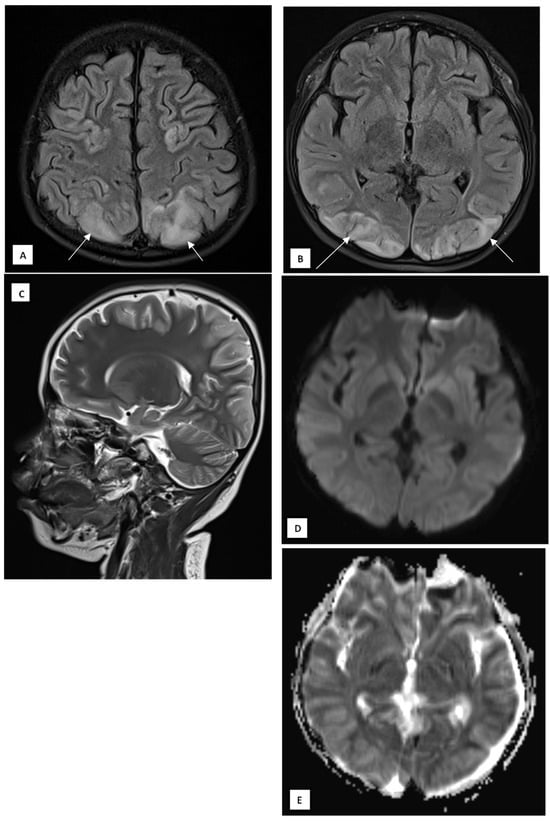

On day 9, the patient’s GCS improved to E4M6V5, with the resolution of fever and seizures. However, he developed sudden blurry vision, headache, and vomiting, without clinical seizures. Ophthalmological examination revealed normal funduscopy but significantly reduced visual acuity (1/300 bilaterally). His blood pressure was elevated to 147/89 mmHg, HR 145 bpm, RR 22 breaths/min, and temperature 37.9 °C. Brain MRI was performed on a 1.5T GE Healthcare scanner with multiplanar T1-weighted imaging (T1WI), T2WI, fluid attenuation inversion recovery (FLAIR), diffusion weighted imaging—apparent diffusion coefficient (DWI-ADC), susceptibility weighted imaging (SWI), with T1 fat saturated (T1FS) pre- and post-contrast. MRI revealed hyperintense lesions in the cortical and subcortical regions of the bilateral parieto-occipital lobes, posterior temporal lobes, left precuneus, bilateral central sulcus areas, and cerebellar periphery, consistent with posterior reversible encephalopathy syndrome (PRES) (Figure 2A–E). There was no contrast enhancement or hemosiderin deposition on SWI.

Figure 2. A 10-year-old boy presented with visual disturbance and seizures. (A,B) Axial T2 dark-fluid images show hyperintense lesions involving the cortical and subcortical regions of the bilateral parieto-occipital lobes, bilateral posterior temporal lobes, left precuneus gyrus, bilateral central sulcus areas, and peripheral cerebellar hemispheres (arrows). (C) Sagittal T2-weighted image confirms the posterior predominance of the lesions. (D) Diffusion-weighted image shows no diffusion restriction. (E) The apparent diffusion coefficient map demonstrates corresponding hyperintensities, consistent with a vasogenic edematous process.

The proposed mechanism involves immune-mediated endothelial dysfunction triggered by cytokine release in MIS-C, leading to cerebral autoregulatory failure and increased vascular permeability [2,6]. Several immunology panels, such as immunoglobulins, were raised in MIS-C patients, raising the possibility of autoimmune components [7]. Unfortunately, due to resource constraints at that time, these panels could not be checked in our patient. The child’s mild hypertension likely compounded the process, causing reversible blood–brain barrier disruption. The absence of diffusion restriction and the presence of high ADC values supported a vasogenic pattern, correlating with the complete clinical recovery.

This case highlights that PRES is associated with reversible neurological complications in MIS-C. The temporal sequence, systemic inflammation, transient hypertension, seizures, and visual loss match the classic presentation of PRES [1,2]. MRI confirmed bilateral parieto-occipital and posterior temporal cortical–subcortical hyperintensities, consistent with vasogenic edema rather than cytotoxic injury. The normal CT findings emphasize the superior sensitivity of MRI in detecting PRES [5].